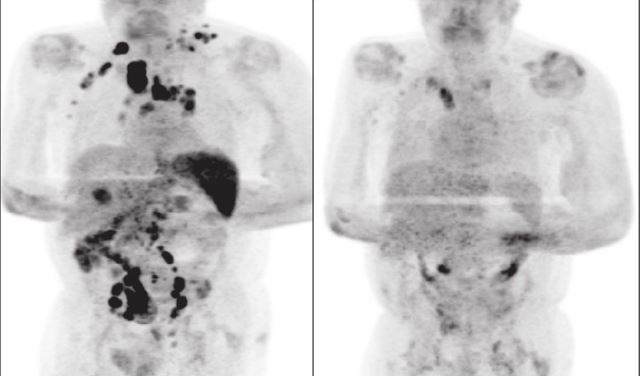

Cuatro meses después, notaron que la inflamación de los ganglios se había reducido y una exploración por tomografía PET reveló una remisión generalizada del linfoma. El cáncer había retrocedido notablemente.

Fuente: La República / Foto: Challenor et al.